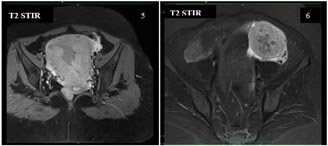

A 40 years old nulliparous premenopausal woman, presented to the gynaecology OPD with a chief complaint of abnormal uterine bleeding and pain in the lower abdomen, predominantly towards left side since an year. The patient had no significant relevant past history or risk factors. The clinical examination of the abdomen revealed no palpable mass. Abdominal ultrasound revealed a solid heterogeneously hypoechoic mass lesion arising from the left ovary, measuring approximately 55x53x50mm and showing moderate colour flow on colour doppler. A moderately enlarged uterus with increase in endometrial thickness was also identified (24 mm). No suspicious abdominal lymphadenopathy was noted. MRI Pelvis showed a single large well defined moderately enhancing, mixed predominantly solid lesion measuring approximately 60x58x53mm (MLXCCXAP) in the left adnexa, which is heterogeneously hypointense on T1W, Isointense with central hypointense areas on T2W, heterogeneously hyperintense with central hypointense areas on T2W/STIR and showing no restricted diffusion on DWI. Uterus appears moderately enlarged with multilobulated heterogenous diffuse moderately enhancing solid areas and non-enhancing cystic areas within the endometrial cavity. No suspicious pelvic lymphadenopathy was noted. Serum CA-125 concentration was elevated,95 U/mL (normal range <35 U/mL). After the positive frozen section pathological examination of the left ovary, the patient underwent a total abdominal hysterectomy, bilateral salpingo-oophorectomy, bilateral pelvic and para-aortic lymphadenectomy, and omentectomy. Pathological findings revealed a well-differentiated endometrioid carcinoma of the left ovary and a well-differentiated endometrioid carcinoma of the endometrium. The patient did not receive any adjuvant chemotherapy or radiotherapy and was suggested for a regular follow-up. Up to the last follow-up visit (April 2021), the patient had no recurrence.

Figure 11                                      Figure 12